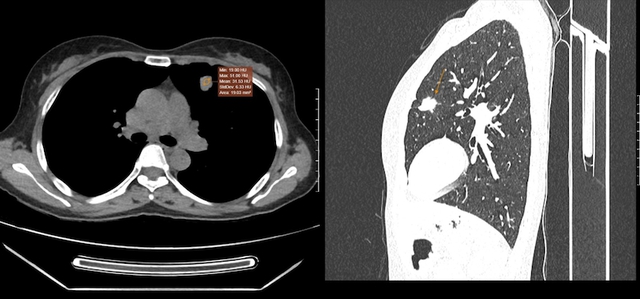

Qua thăm và thực hiện các xét nghiệm, kết quả đều chưa ghi nhận dấu hiệu đáng lo ngại. Tuy nhiên, kết quả chụp cắt lớp vi tính (CT) lồng ngực có tiêm thuốc cản quang cho thấy thùy trên phổi trái xuất hiện nốt đặc kích thước 21x14mm, bờ tua gai đồng thời phát hiện hình ảnh nốt giảm tỷ trọng tại tuyến thượng thận trái.

Để xác định bản chất tổn thương, bệnh nhân được chỉ định sinh thiết xuyên thành ngực dưới hướng dẫn của chụp CT. Sau đó mẫu bệnh phẩm được gửi đến Trung tâm Giải phẫu bệnh, kết quả cho thấy, bệnh nhân bị ung thư biểu mô tuyến.